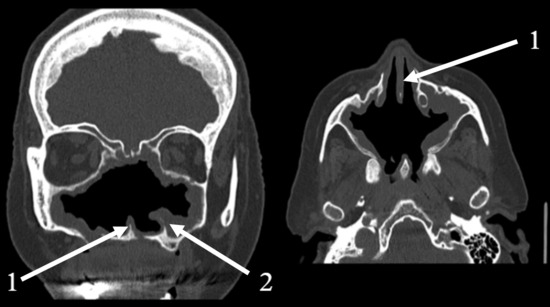

Background and Clinical Significance: Atrophic rhinitis (AR) is a rare, chronic inflammatory condition characterized by progressive atrophy of the nasal mucosa and underlying bone. The present report describes a case of severe secondary AR as a sequela of COVID-19-associated necrotizing rhinitis, highlighting the diagnostic and management challenges posed by multi-drug resistant pathogens and extensive anatomical destruction. Case Presentation: A 75-year-old female developed progressive necrotizing rhinosinusitis with osteomyelitis following a COVID-19 infection. Computed tomography (CT) confirmed an osteolytic process and subsequent profound anatomical destruction, while histopathology ruled out invasive fungal disease. The resulting cavity was colonized by multi-drug resistant Pseudomonas aeruginosa and Staphylococcus aureus. Management and Outcome: Management focused on preventing crust formation through a structured “nasal rest” protocol, supplemented by cleansing nasal douching with a surfactant (baby soap) and mechanical crust removal. This treatment led to significant clinical improvement, with reduced crusting and complete resolution of ozena symptoms. Conclusions: This case illustrates the potential for SARS-CoV-2 infection to precipitate severe necrotizing sinonasal complications leading to secondary AR. It demonstrates the efficacy of a management strategy focused on mechanical cleansing and nasal rest, particularly when conventional antibiotic therapy is limited by extensive drug resistance. Full article

Show Figures

Figure 1